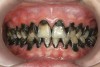

Fig 8. Use of 38% SDF to arrest rampant caries in a young teenager. Fig 8: Pre-treatment intraoral frontal view of rampant caries. Fig 9: Frontal view of arrested caries after consecutive application of SDF for 3 weeks. (images from Chu, et al, 201436 [reprinted with approval])

Figure 8